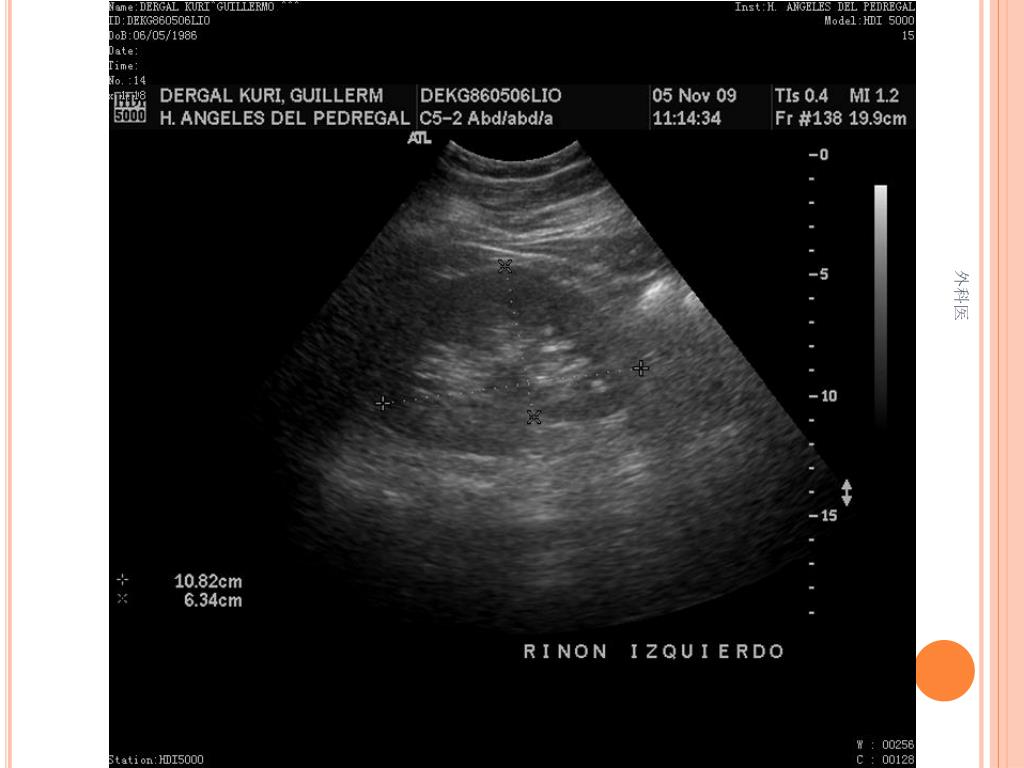

21. 外科医

44. Tips • Leucocitos Mas de 20000/ml • Mas de 20% de la apéndices no se llenan con el bario por enema. • USG sensibilidad del 85% y Especificidad de mas 90% para Apendicitis Aguda. • TAC de Abdomen cortes de 5mm, sensibilidad y especificidad del 90% para dolor abdominal. • Analisis de 75000, taza de apendice negativa de 6% Hombres y 13% Mujeres 外科医